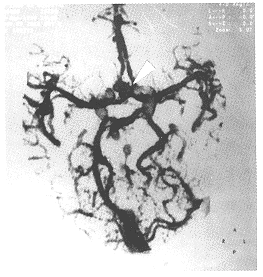

图4

图5

图6

图4、5、6箭号所指为前交通动脉动脉瘤